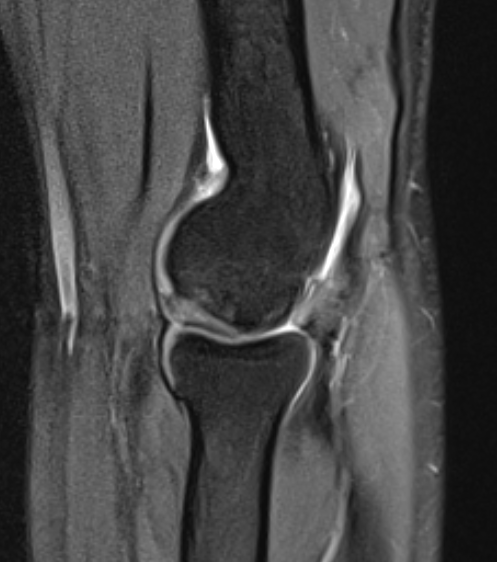

MRI

Fluid interface denotes detachment / instability

MRI Classification

Stable

- cartilage intact

- no fluid behind lesion

Unstable

- cartilage breach

- fluid behind lesion